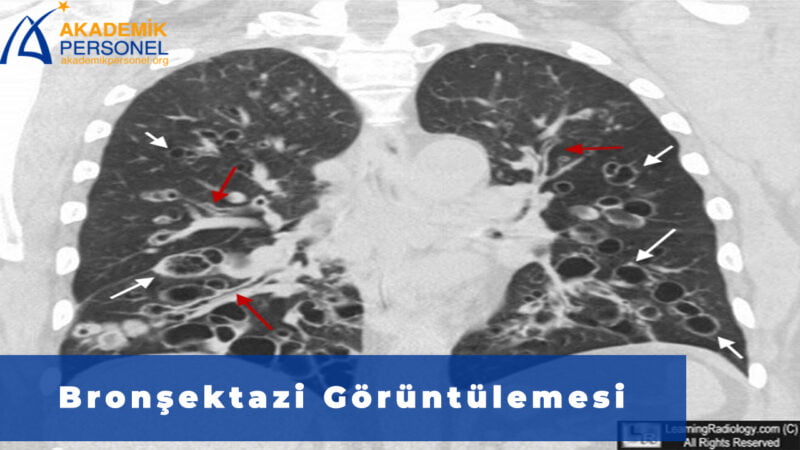

Bronşektazi Tanısı Nasıl Konur ?

Bronşektazi tanısı öykü, fizik muayene ve tanı testleri sonucunda konur. İlk olarak belirtilerin ortaya çıkış zamanını, kötüleşip kötüleşmediği ve arada alevlenme olup olmadığı değerlendirilir. Fizik muayenede solunum sesi dinlenir. Bunun yanında kalp atış hızına, nefes alma hızına ve kan basıncına bakılır. Tüm bunları doktorunuz genel olarak değerlendirir ve hangi tanı testlerine gerek olup olmadığına karar verir.

Tüm bu değerlendirmelerin sonucunda doktor tarafından istenecek tanı testleri ise şu şekildedir:

- Görüntüleme Testleri : Görüntüleme testi olarak röntgen ve bilgisayarlı tomografi (BT) kullanılır. Bunların hangisini kullanılacağı hastalığın durumu ve cihaz imkanlarına göre değişmektedir.